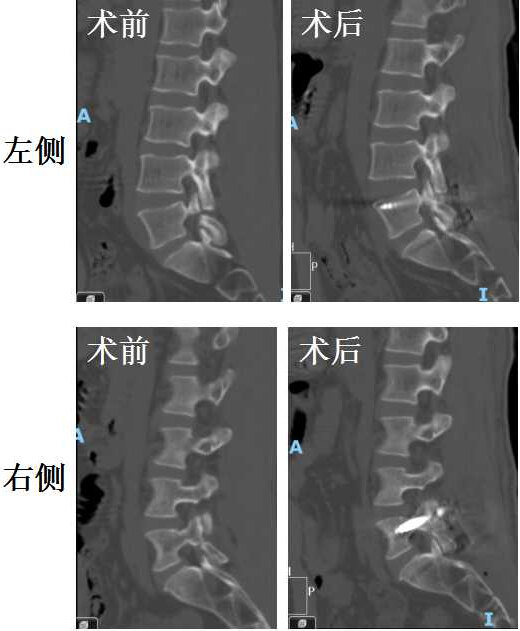

峡部裂,双侧峡部裂!疼的这么难受保守治疗效果也不好了合计合计那就做手术呗!而且小李子这间盘还挺年轻,先不动它,就打钉子取骨头把峡部修一修。效果还挺好!

手术前后CT对比示峡部裂修补情况